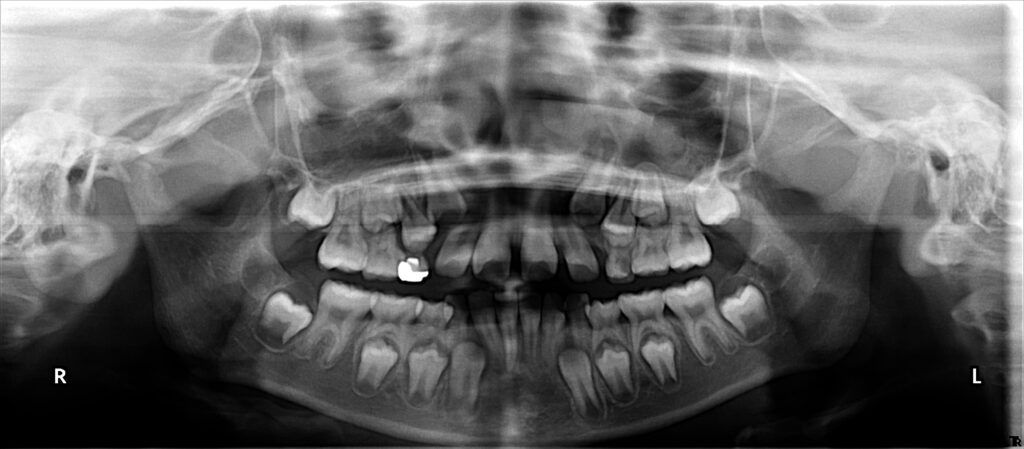

治療前

概要

- 初診:2016年、9歳女児

- 主訴:出っ歯と歯の隙間がきになる。

- 診断:2級過蓋咬合、上下永久歯(犬歯)萌出スペース不足

- 治療方針:非抜歯で行う。虫歯予防(フッ素)、歯磨き指導、上下拡大床→咬合関係改善のツインブロック(2級→1級関係へ)→マウスピース矯正→下親知らずの抜歯、保定→メンテナンス